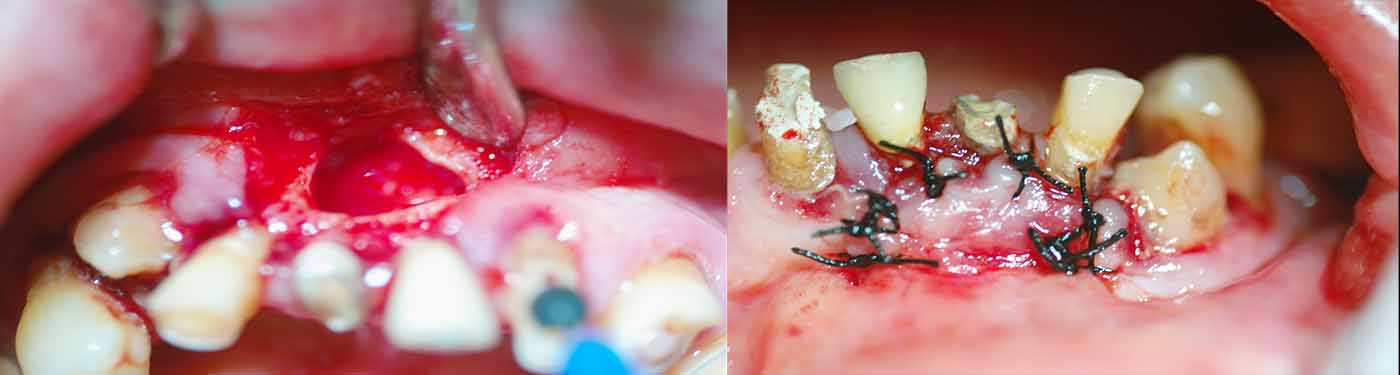

Ακολουθώντας τις πιο σύγχρονες τεχνολογικές εξελίξεις, έχουμε ενσωματώσει προηγμένα εργαλεία και μεθόδους στην ενδοδοντική θεραπεία. Χρησιμοποιούμε περιστροφικά εργαλεία τελευταίας γενιάς, σύγχρονα συστήματα έμφραξης με θερμοπλαστικοποιημένη γουταπέρκα, καθώς και ακριβείς συσκευές ανεύρεσης του μήκους των ριζικών σωλήνων, όπως το apex locator. Επιπλέον, η κλινική μας διαθέτει ψηφιακή ακτινογραφία και CBCT (αξονική τομογραφία) για την ακριβή διάγνωση και τον βέλτιστο σχεδιασμό της θεραπείας.

Ο συνδυασμός της τεχνολογίας με τη λεπτομερή προσέγγιση και την εξατομικευμένη φροντίδα που προσφέρουμε, μας επιτρέπει να επιτυγχάνουμε άριστα αποτελέσματα ακόμα και στις πιο απαιτητικές περιπτώσεις. Στόχος μας είναι η διάσωση των φυσικών δοντιών, διασφαλίζοντας τη μακροχρόνια υγεία και λειτουργικότητα του στόματος των ασθενών μας.